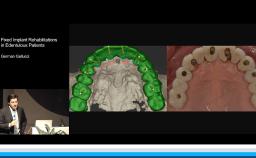

This lecture explains the trends in implant dentistry in a digital world: using digital impressions to obtain milled, printed, or digital casts; designing virtual prostheses via digital diagnostic wax-ups; and incorporating the patient’s cone beam CT into a digital workflow. This practice philosophy embraces prosthodontic-driven treatment planning in completely and partially edentulous arches through identifying the ideal prosthesis and creating prefabricated components. This presentation further demonstrates how this philosophy can lead to uneventful treatment that minimizes complications. The speaker emphasizes the key relationships between teeth, lips, and the residual ridge that indicate the optimal three-dimensional position for implant prostheses, and he advocates for the use of interim prostheses.

- describe the digital workflow for implant therapy